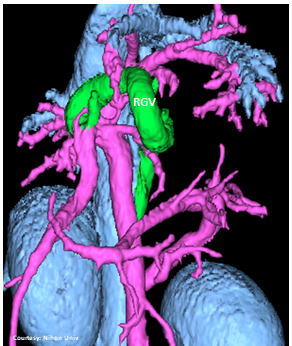

Does the RIGHT GASTRIC VEIN (RGV) contribute blood to the shunt?

WEISSE 2022